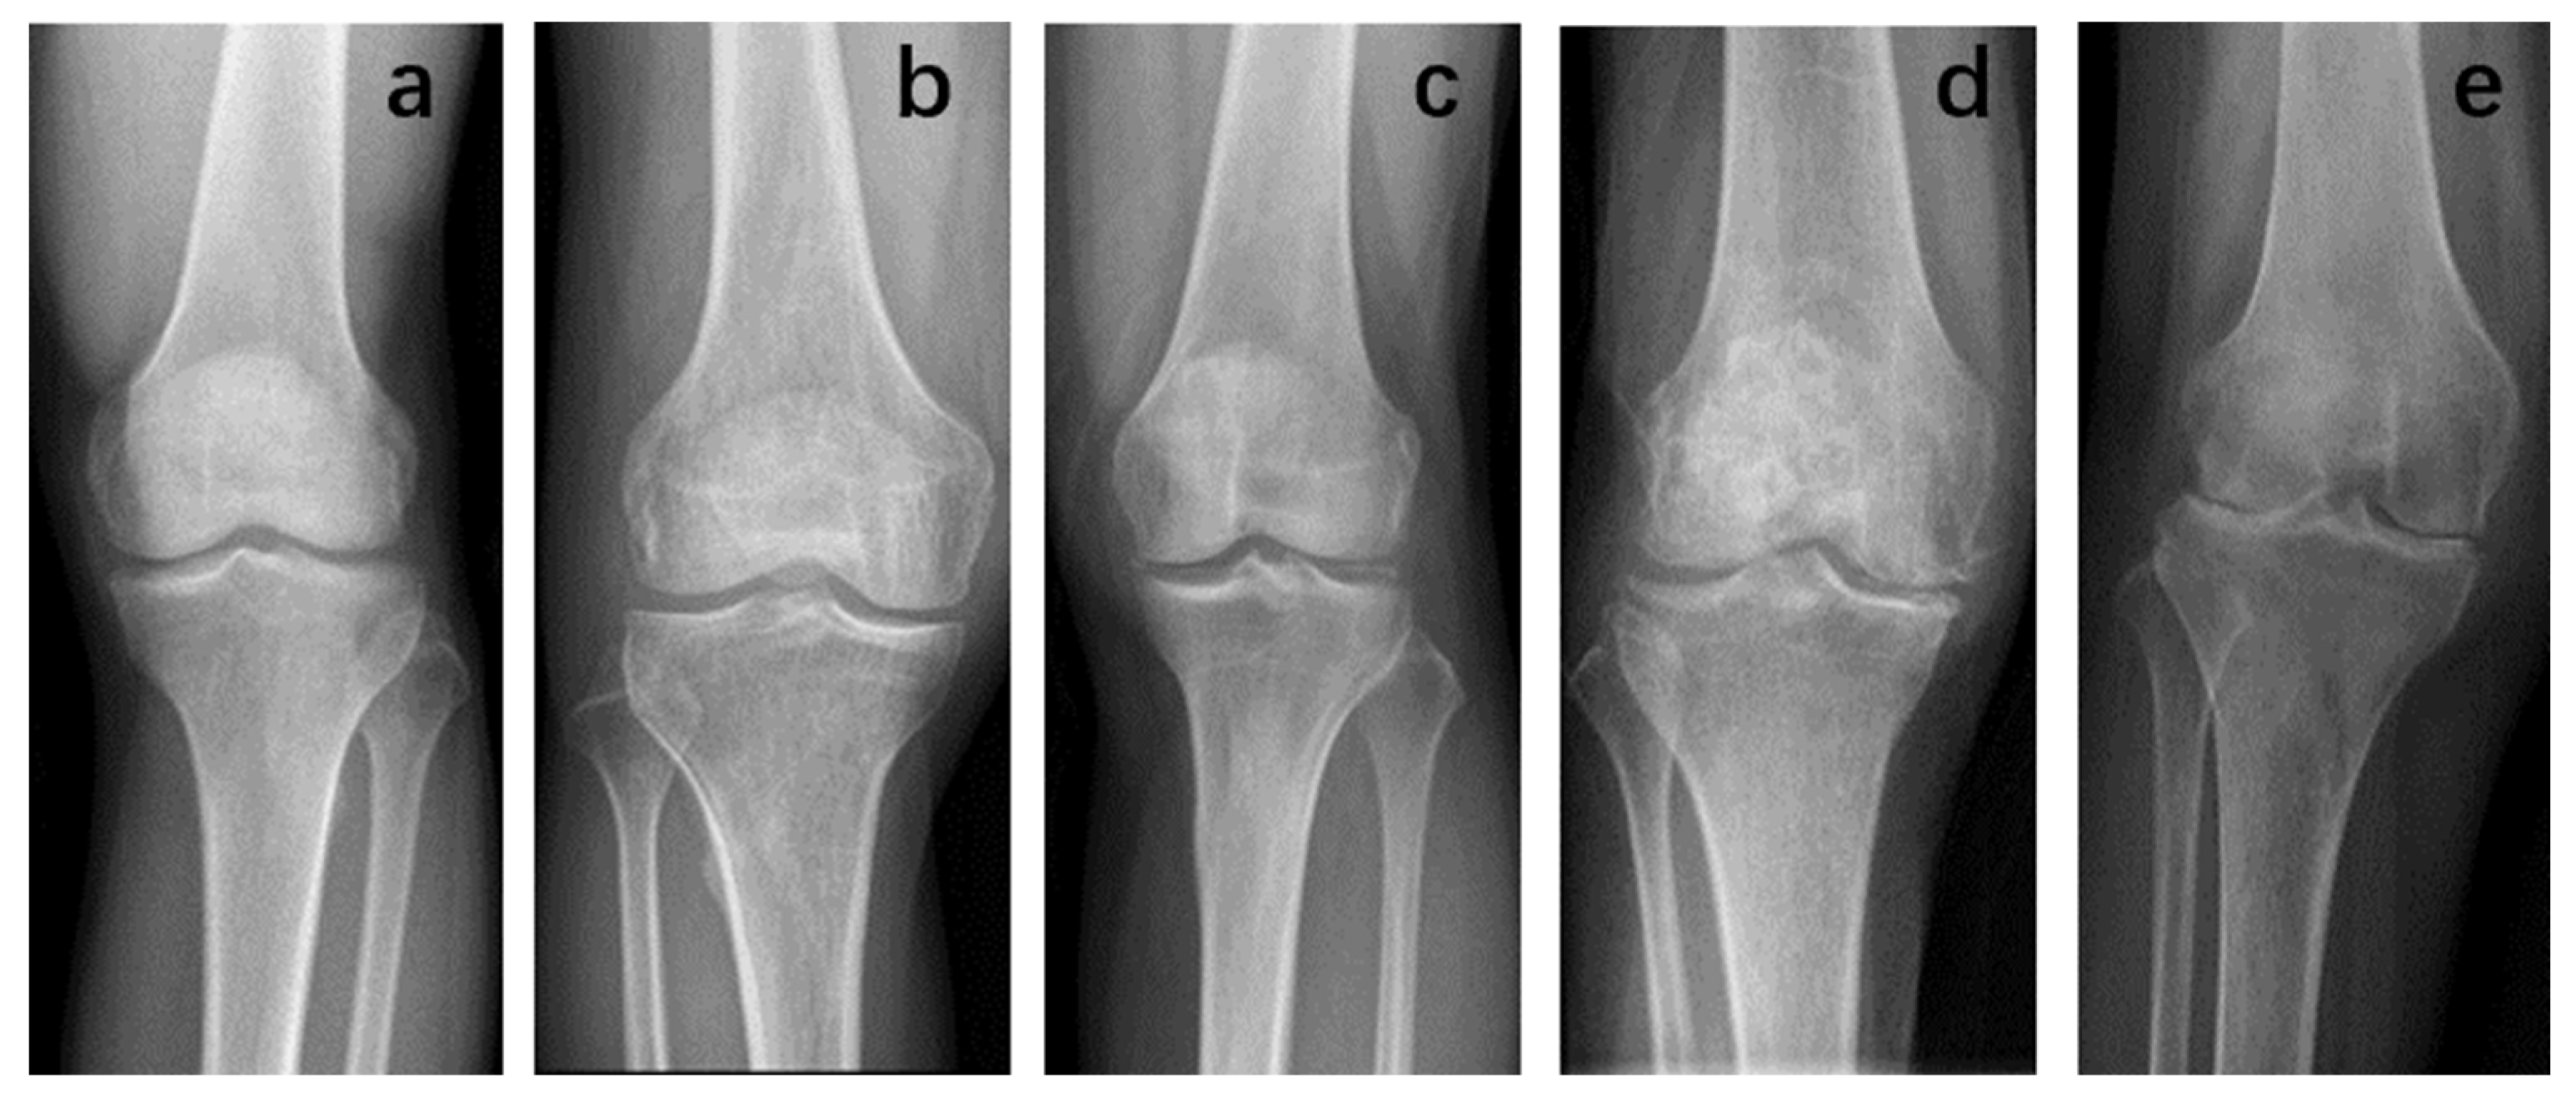

According to the K-L classification of knee X-ray evaluation: grade 0, no osteophytes and narrowing of the joint space; grade I represents no obvious narrowing of the joint space, possible osteophytes; grade II, mild osteophytes, normal or suspicious narrowing of the joint space; grade III, moderate Osteophytes with stenotic subchondral sclerosis of the joint; and grade IV represents obvious osteophytes, with markedly narrowed joint septa and severe sclerosis of the subchondral bone (Figure 2).

Figure 2.

K-L classification. The patient was graded on an X-ray of the knee joint according to the method previously described. (a) Grade 0; (b) Grade I; (c) Grade II; (d) Grade III; (e) Grade IV.

The K-L classification is the most widely used clinical imaging method for osteoarthritis. It scans the knee joints of patients with X-rays and evaluates the formation of osteophytes, joint space, cartilage and subchondral bone. OA is divided into grades I-IV [26]. Previously, some researchers believed that IPFP signal intensity on MRI could predict the occurrence of radiological OA (ROA) [27]. This pattern was also found in our study: an increase in IPFP inflammation score was always accompanied by a higher K-L grade of osteoarthritis; that is, there was a significant correlation between IPFP inflammation score and K-L grade under MRI.